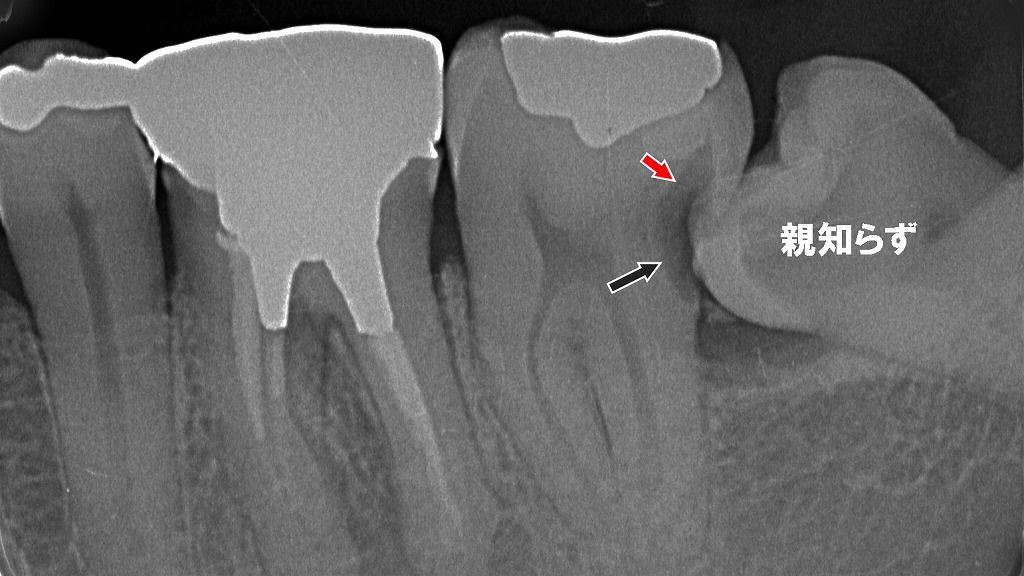

📍下顎孔伝達麻酔を打つ位置

白い点の部位から針を挿入

写真の白丸の位置(親知らずのさらに奥) から針先を刺入し、2cm程奥に針を進めます。

下顎孔の位置は個人差が大きく外から見えないため、正確に場所を特定することは出来ません。従って、勘に頼ることになり効果的な麻酔をかけるにはかなりの熟練を要します。

下顎孔を完全に麻酔が出来れば、無痛治療が可能です。